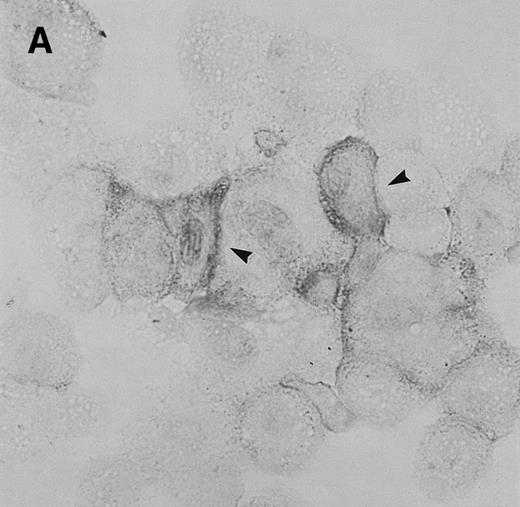

To determine whether CNS-ECs respond to Et-1 by producing IL-8, the cultures were first grown to confluency and then repeatedly treated with Et-1 at 24-hour intervals for the required experimental period. It was noted that subconfluent cultures were generally less responsive to Et-1; therefore, cultures used in this study were greater than 90% confluent. Furthermore, the addition of Et-1 only at initiation of the experiment resulted in a reduced effect. The results using the ELISA technique on culture supernatants showed that 24-hour samples expressed little increased IL-8 production compared with control levels (Fig 1). Each point represents quadruplicate samples; the SEM was usually less than 5%. The concentration of IL-8 in the culture supernatant of 48- and 72-hour cultures increased twofold and threefold, respectively. To determine whether IL-8 protein was synthesized before 48 hours, the kinetics of IL-8 production were analyzed on a single cell level. CNS-ECs were treated with Et-1 for 6, 24, and 48 hours and then examined using immunocytochemistry. Results in Fig2A demonstrate that as early as 6 hours, 20% of the cells were IL-8–positive. After 24 hours, 50% to 70% of the cells stained for IL-8 (Fig 2C). The 48-hour cell preparations appeared similar to the 24-hour cultures (data not shown). Control untreated cultures exhibited less than 3% positivity (Fig 2B and D). Irrelevant isotype-matched monoclonal antibody did not show significant staining. To determine the optimal concentration of Et-1, a range of Et-1 concentrations were examined. Results in Fig3 show that at 10−8 to 10−6 mol/L Et-1, there was a significant increase of IL-8 production compared with controls; at Et-1 concentrations above 10−6 mol/L, cell morphology was altered, and adhesion decreased while IL-8 levels remained constant (data not shown). Based on these results, all experiments presented here used 10−7 mol/L Et-1 unless otherwise stated. To confirm that the observed twofold to threefold increase in IL-8 production with Et-1 stimulation is consistent and reproducible, 11 independent experiments were performed comparing the supernatants from control and Et-1–treated cells. Results in Fig 3B demonstrate that Et-1 significantly (P < .001) increased IL-8 production in CNS-ECs.

Immunocytochemistry of Et-1–treated CNS-ECs. Cell preparations of treated and untreated cultures were stained with monoclonal anti-human IL-8 after 6 hours (A, treated; B, control) or 24 hours (C, treated; D, control). Arrows indicate positive cells (original magnification × 400).